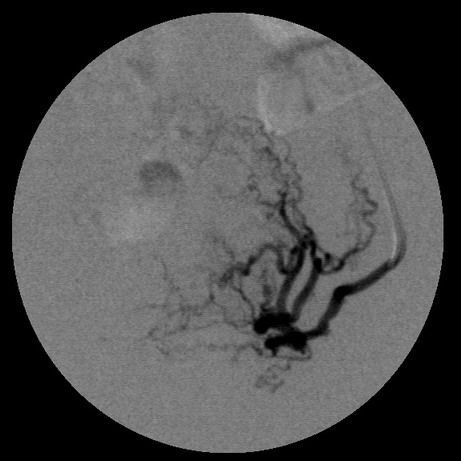

女,35岁,子宫多发肌瘤

子宫动脉增粗,分支数量增多,迂曲,染色明显并排空延迟

栓塞剂用的是进口pva,二瓶,几千块呀,栓塞面积应该不大吧,呵呵